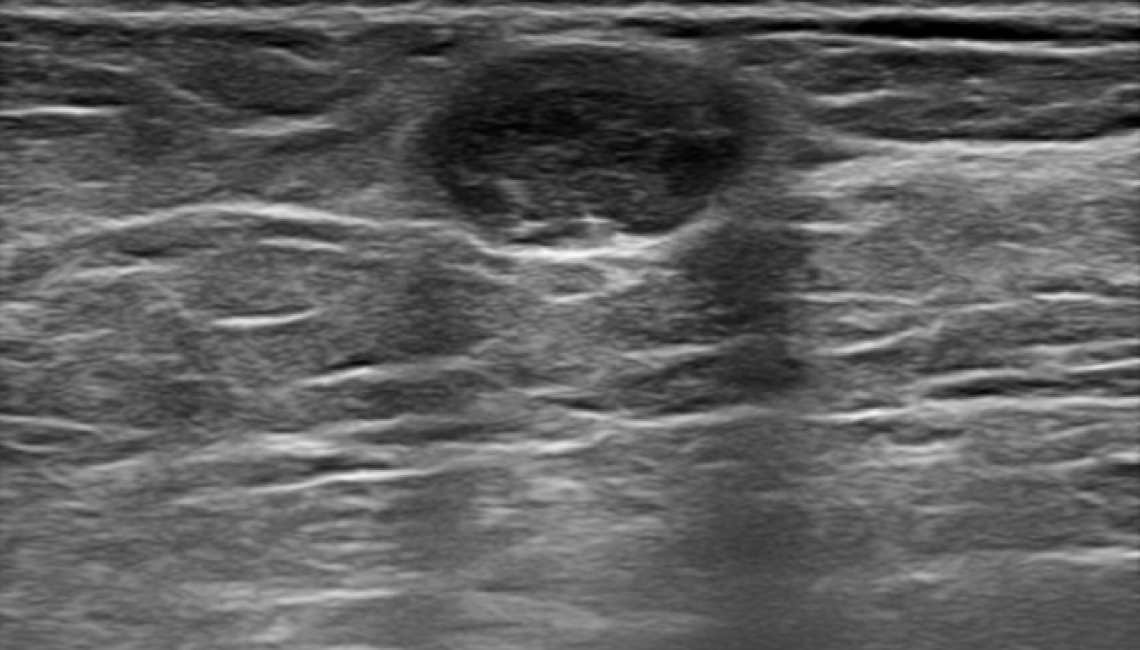

Quantitative Ultrasound Solution for Breast Cancer

Int-BUS quantitatively restores and provides the biomechanical characteristics of cells. Based on this analysis, it can indicate whether the tissue is benign or malignant.

Int-BUS restores and analyzes the cellular characteristics of tumors. Even in cases where differentiation is difficult based on imaging findings, an accurate diagnosis is possible by analyzing the cellular characteristics.